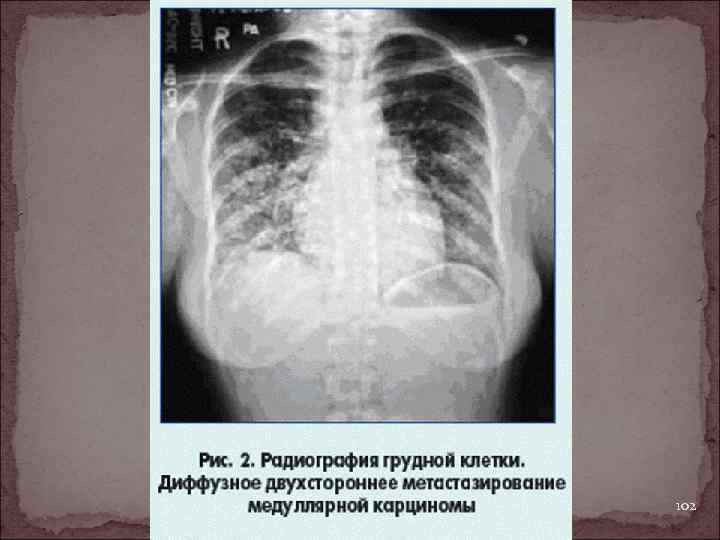

102